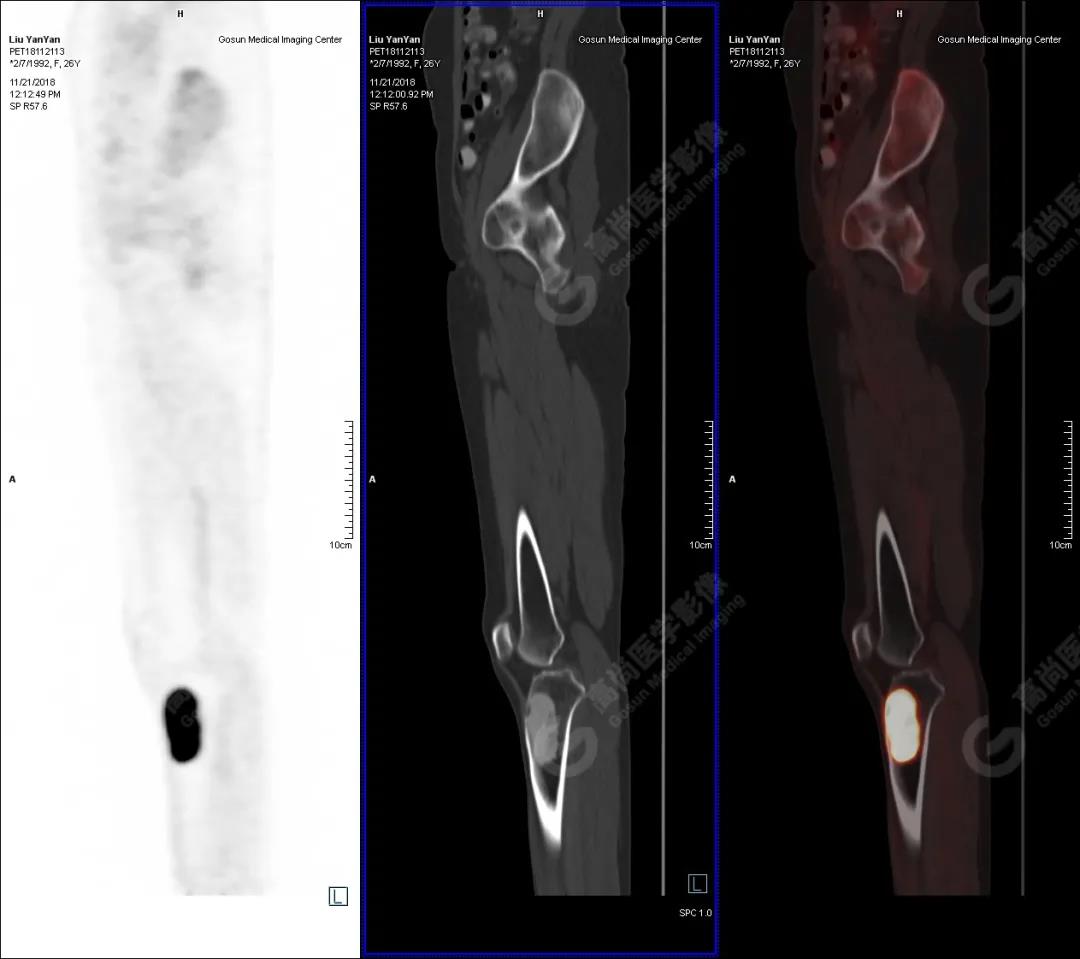

病史摘要

女性 ,26歲,右膝關(guān)節(jié)疼痛9個月,DR及MR檢查提示右側(cè)脛骨占位。既往無外傷史、無糖尿病、高血壓、肝炎、結(jié)核及手術(shù)史。

PET/CT檢查

PET/CT表現(xiàn)

右側(cè)脛骨上段髓腔內(nèi)見卵圓形塊狀高密度影,長徑與脛骨長軸平行,邊界清楚,密度欠均勻,CT值介于287.0Hu~425.0Hu,放射性攝取增高,SUV最大值為15.8,平均值為13.1。

PET/CT診斷

右側(cè)脛骨良性骨腫瘤樣病變,不除外非骨化性纖維瘤。

病理診斷

隨訪結(jié)果:活檢病理確診非骨化性纖維瘤。